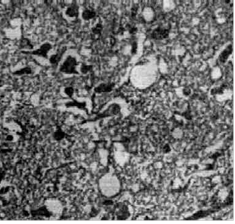

Без признаков воспаления в головном и иногда спинном мозге обнаруживаются признаки гибели нервных клеток и их отростков. В мозговой ткани образуются вакуоли, количество которых постепенно увеличивается. На основе таких первично-дегенеративных процессов (без признаков воспаления!) в головном и иногда спинном мозге медленно и постепенно развивается картина формирования так называемого "губкообразного состояния" - мозговая ткань на гистологических срезах выглядит как губка из-за огромного количества вакуолей (рис.1 и 2).

Кроме того, в мозговой ткани могут образовываться и накапливаться амилоидные бляшки и, что не менее характерно, разрастается глиозная ткань мозга. И больше ничего! Ни иммунологических проявлений, ни признаков воспаления.